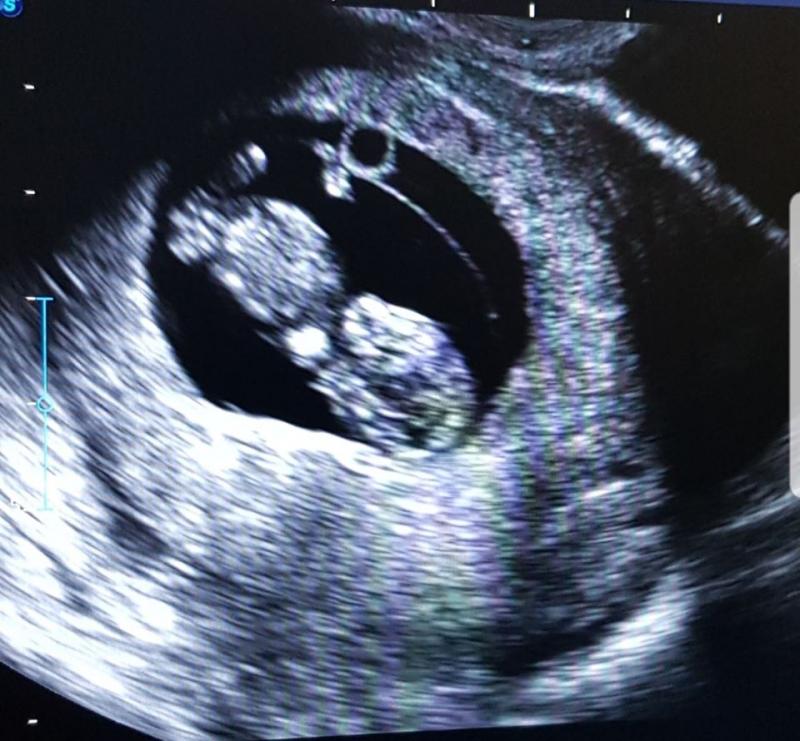

Ecografia făcută publică pe rețeaua socială este, de asemenea, însoțită de un mesaj, în cadrul căruia a dezvăluit că va deveni mamă de baiat.